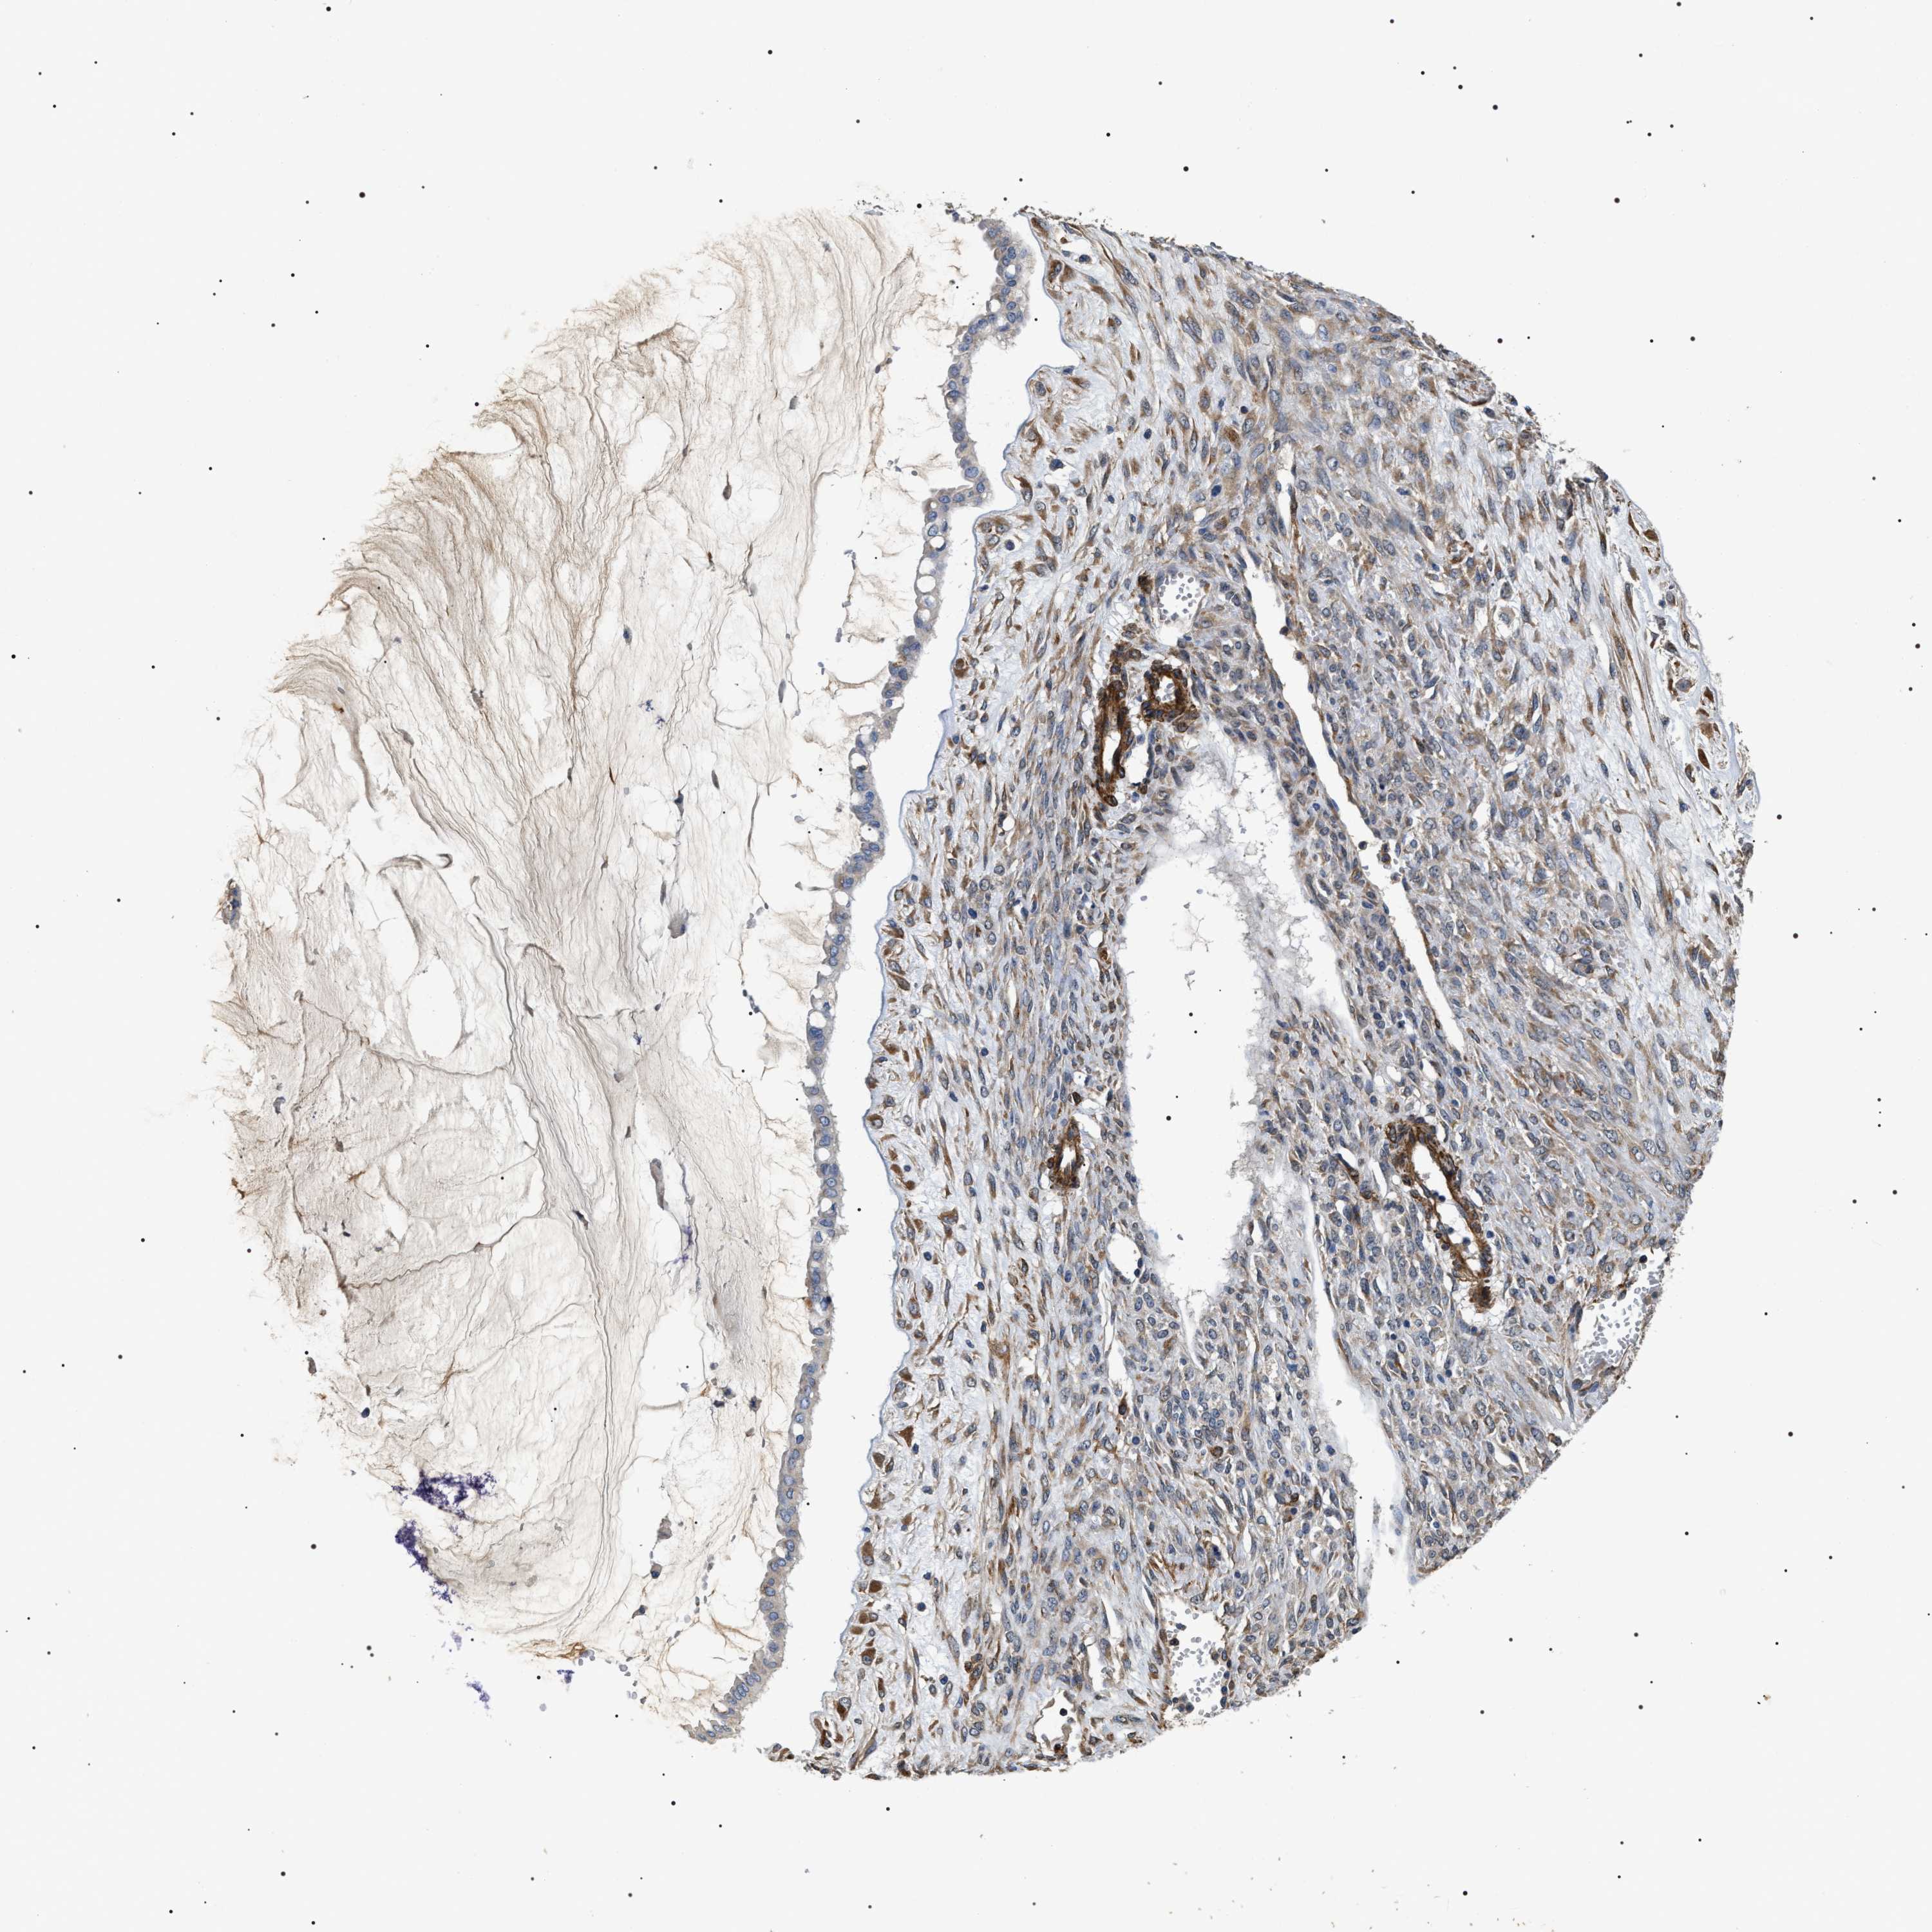

OVARIAN CANCER - Protein expressioni

A mouse-over function shows sample information and annotation data. Click on an image to view it in a full screen mode. Samples can be filtered based on level of antibody staining by selecting one or several of the following categories: high, medium, low and not detected. The assay and annotation is described here.

Note that samples used for immunohistochemistry by the Human Protein Atlas do not correspond to samples in the TCGA dataset.

Antibody stainingi

Antibody staining in the annotated cell types in the current human tissue is reported as not detected, low, medium, or high, based on conventional immunohistochemistry profiling in selected tissues. This score is based on the combination of the staining intensity and fraction of stained cells.

Each image is clickable and will lead to virtual microscopy that enables deeper exploration of all samples and also displays staining intensity scores, fraction scores and subcellular localization as well as patient and tissue information for each sample.

Antibody HPA020386

Staining

High

Medium

Low

Not detected

Intensity

Strong

Moderate

Weak

Negative

Quantity

>75%

75%-25%

<25%

None

Location

Nuclear

Cytoplasmic/membranous

Cytoplasmic/membranous,nuclear

Cystadenocarcinoma, serous, NOS

Carcinoma, endometroid

Cystadenocarcinoma, mucinous, NOS

Carcinoma, NOS